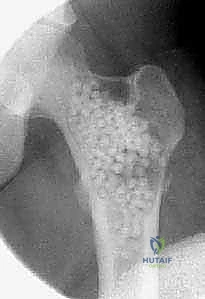

تُظهر هذه الأشعة السينية (X-ray) كيس عظم أحادي الغرفة (UBC) في الجزء العلوي من عظم العضد. لاحظ كيف أن الكيس يسبب ترققاً في قشرة العظم دون أن يخترقها.

- الأشعة السينية (X-rays):

- هي الخطوة الأولى والأساسية.

- في الـ UBC، تظهر الآفة كمنطقة شفافة (سوداء) مركزية داخل العظم. وهناك علامة مميزة تُسمى "علامة الورقة المتساقطة" (Fallen Leaf Sign)، حيث تسقط قطعة صغيرة من قشرة العظم المكسورة داخل الكيس المملوء بالسائل، وهي علامة مؤكدة بنسبة 100% تقريباً على الـ UBC.